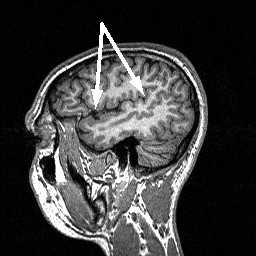

МРТ головного мозга. Срединный сагиттальный срез. Намёт мозжечка (стрелка).

МРТ головного мозга. Латеральный сагиттальный срез. Центральная борозда (стрелка).